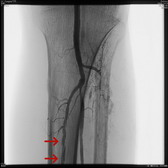

可怕的LEADDP 糖尿病下肢血管病变(LEADDP)可致患者肢体麻木、疼痛,间歇性跛行,乃至坏疽(糖尿病足),截肢率高达40 %以上。LEADDP是糖尿病致残、致死的主要原因,糖尿病患者因LEADDP造成的截肢,要比非糖尿病患者高5到10倍以上。先进的DSA + 微创介入 1、选择性血管造影(DSA)是LEADDP诊断的金标准。 2、微创介入治疗优点: 创伤小,仅有一2-3 mm的穿刺创口 成功率高:目前其成功率达85-90 % 保肢率高:术后病人截肢率可从40 %降为4 %左右 早发现早治疗:越早治疗效果越好.独创的微创介入 + HBO + bFGF综合治疗途径 1、DSA + 微创介入 2、高压氧(HBO)物理疗法:大型空气加压舱,治疗压力0.2 MPa,面罩吸纯氧30 min 3、基于重组成纤维细胞生长因子(bFGF)局部换药.